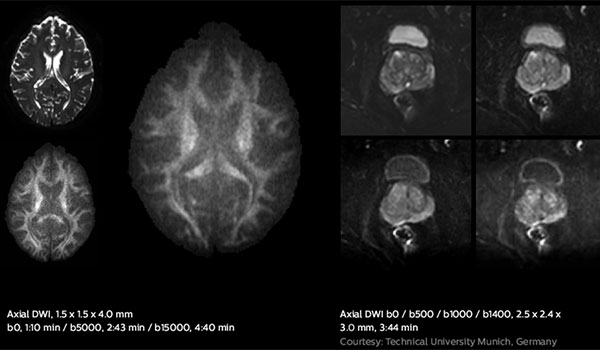

Enjoy consistent, excellent image quality for multiple anatomies. Versatile arrangements of dStream coils work together with ExamCards tailored for RT to provide high-contrast images with high geometric fidelity. Quickly execute complete imaging protocols for prostate, female pelvis, brain, head and neck, and spine.